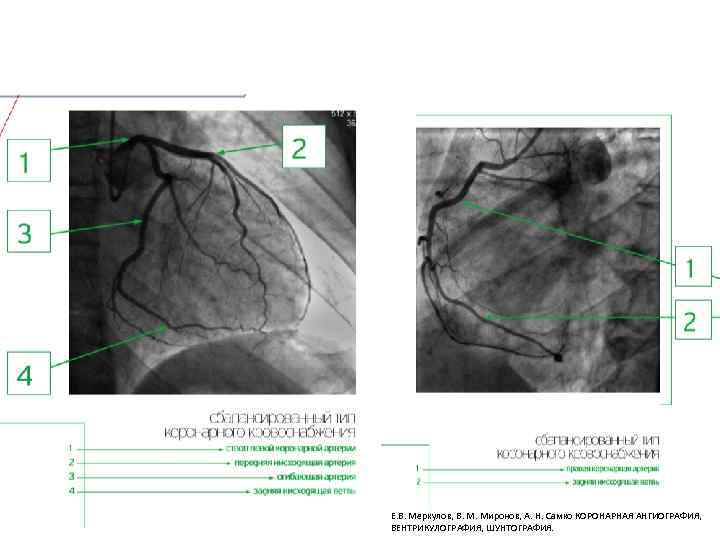

Типы кровоснабжения сердца Е. В. Меркулов, В. М. Миронов, А. Н. Самко КОРОНАРНАЯ АНГИОГРАФИЯ, ВЕНТРИКУЛОГРАФИЯ, ШУНТОГРАФИЯ.

Е. В. Меркулов, В. М. Миронов, А. Н. Самко КОРОНАРНАЯ АНГИОГРАФИЯ, ВЕНТРИКУЛОГРАФИЯ, ШУНТОГРАФИЯ.